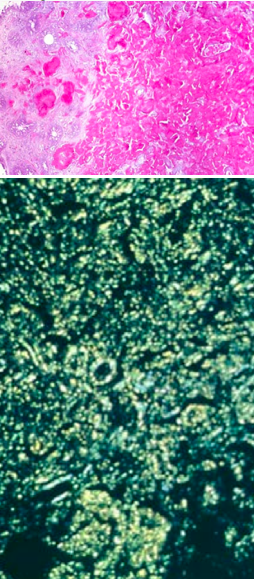

What observations do you have of this patient’s liver?

Note the nodules of hepatocytes surrounded by bands of fibrosis. This is characteristic of cirrhosis. Note the pigment in Kupffer cells and bile duct epithelial cells. Note below the Prussian blue stain indicating hemochromatosis as the culprit.

How do you confirm that this patient had hemochromatosis?

Despite presence of brown deposits, Prussian-blue stain will confirm that it is iron and not lipofuscin.